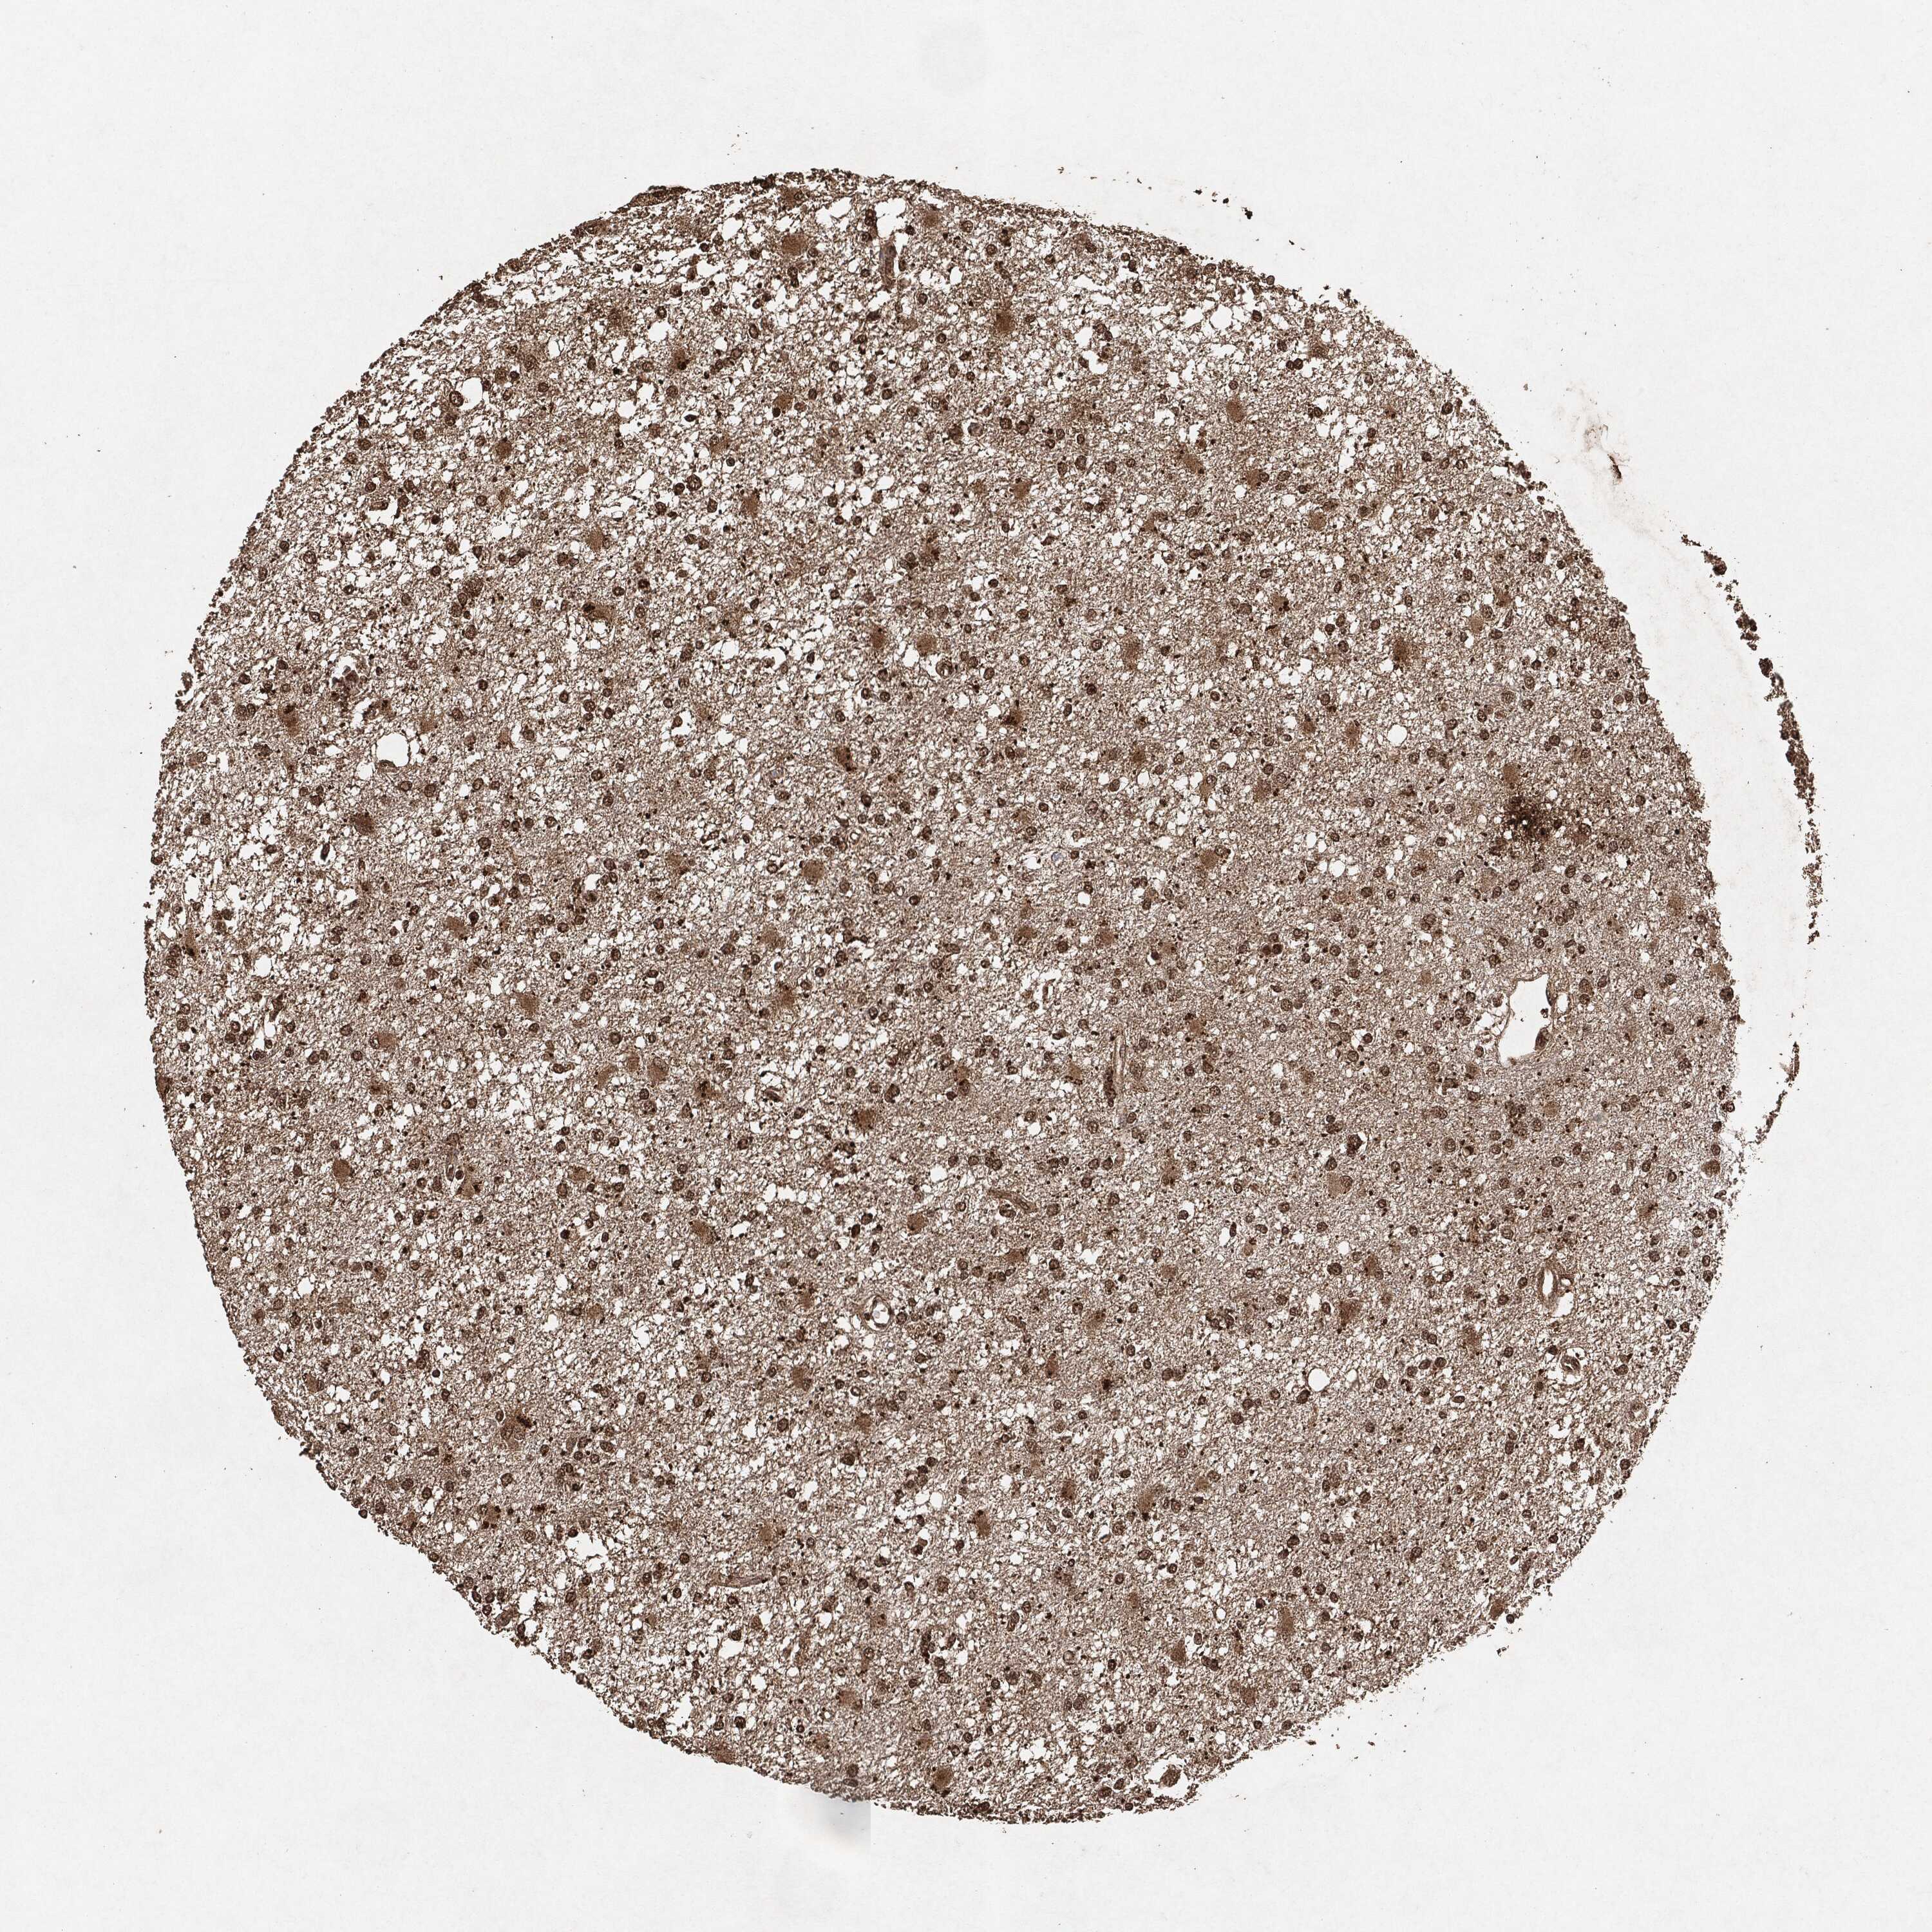

GLIOMA - Protein expressioni

A mouse-over function shows sample information and annotation data. Click on an image to view it in a full screen mode. Samples can be filtered based on level of antibody staining by selecting one or several of the following categories: high, medium, low and not detected. The assay and annotation is described here.

Note that samples used for immunohistochemistry by the Human Protein Atlas do not correspond to samples in the TCGA dataset.

Antibody stainingi

Antibody staining in the annotated cell types in the current human tissue is reported as not detected, low, medium, or high, based on conventional immunohistochemistry profiling in selected tissues. This score is based on the combination of the staining intensity and fraction of stained cells.

Each image is clickable and will lead to virtual microscopy that enables deeper exploration of all samples and also displays staining intensity scores, fraction scores and subcellular localization as well as patient and tissue information for each sample.

Glioma, malignant, High grade

Glioma, malignant, Low grade

Glioma, malignant, NOS